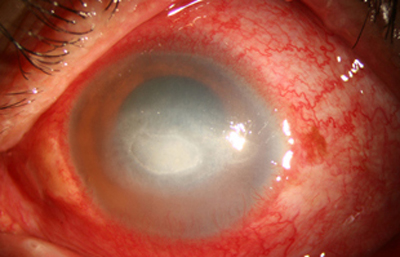

Superficie corneal irregular y grisácea, (Fig. 1, 2) con opácidades granulares en parche y formación de líneas epiteliales elevadas de aspecto granular (Fig. 3), que pueden arborizar dando imágenes de pseudodendritas. Opacidades superficiales satélites. (Figura 4) Inyección ciliar. Ulceración epitelial variante. (Figura 5).

Fig. 1 Síntomas de 15 días evolución

Fig. 2 Síntomas de 25 días evolución

Estas lesiones progresan con la aparición de infiltrados estromales anteriores difusos o focales, (Figura 6) edema circunscrito, y en ocasiones infiltrados en los nervios corneales (Figura 7), (perineuritis, usualmente entre las 1 a 4 semanas de evolución).

En su evolución se observará aumento del edema, agrandamiento y coalescencia de los infiltrados formando un anillo, (Figura 9, 10 y 11) que progresa hacia la formación de un absceso (Figura 12, 13 y 14), queratolisis superficial, adelgazamiento y perforación corneal (Figura 15 y 16).

Limbitis y escleritis anterior difusas.

La vascularización y el hipopion son poco frecuentes en los estadios tempranos de la queratitis. Con el tiempo, en los estados avanzados de invasión estromal, aparecen vasos estromales (Figura 17)